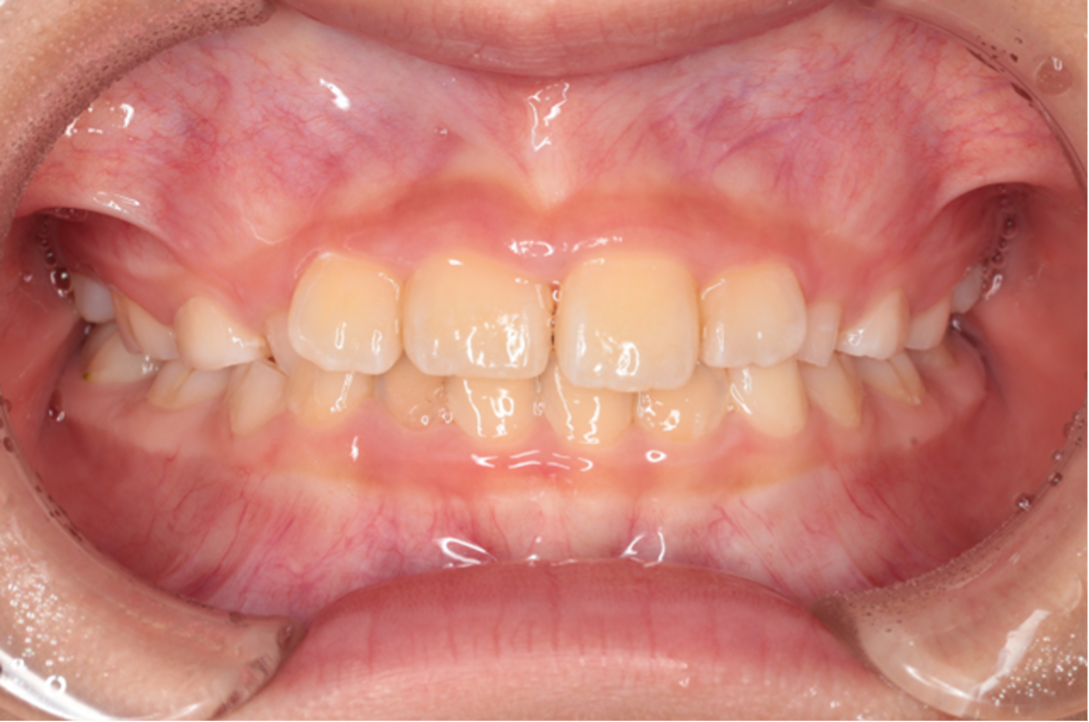

交差している歯並びを改善しました

Under Treatment